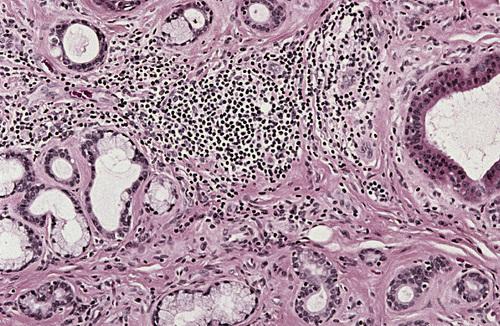

Mucin-filled cystlike cavity beneath the mucosal surface. Minor salivary glands are present below and lateral to the spilled mucin.

mucocele

High-power view showing spilled mucin that is associated with granulation tissue containing foamy histiocytes.

mucocele